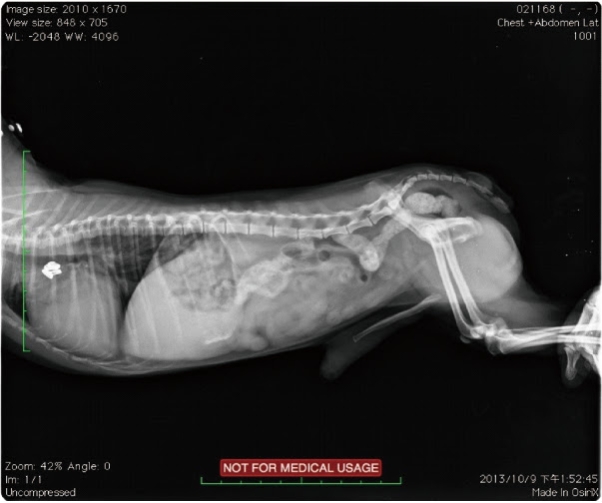

發病年齡,往往都在二到三個月大,通常都是長時間的慢性嘔吐、極度消瘦丶極度飢餓來醫院就診,x光是最好的診斷工具,除了明顕的食道擴張(心基部之前),常常可以發現吸入性肺炎的胸腔影像。

【圖十一】兩個月大的米克斯幼犬, x光下發現食道在心基部之前擴張